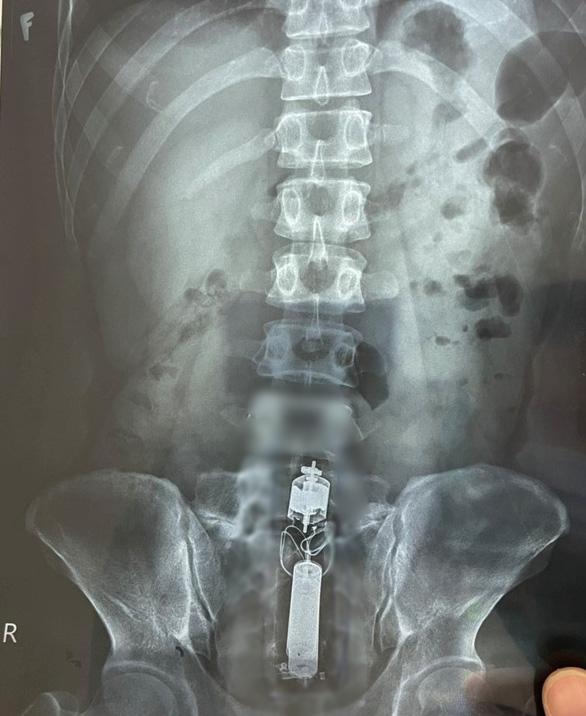

Tại Bệnh viện Quân y 175, sau khi tiến hành thăm khám, chụp X-quang cho bệnh nhân, các bác sĩ phát hiện trực tràng có dị vật hình dạng giống như "của quý" nên quyết định phẫu thuật.

Hình ảnh đồ chơi tình dục mắc kẹt trong trực tràng